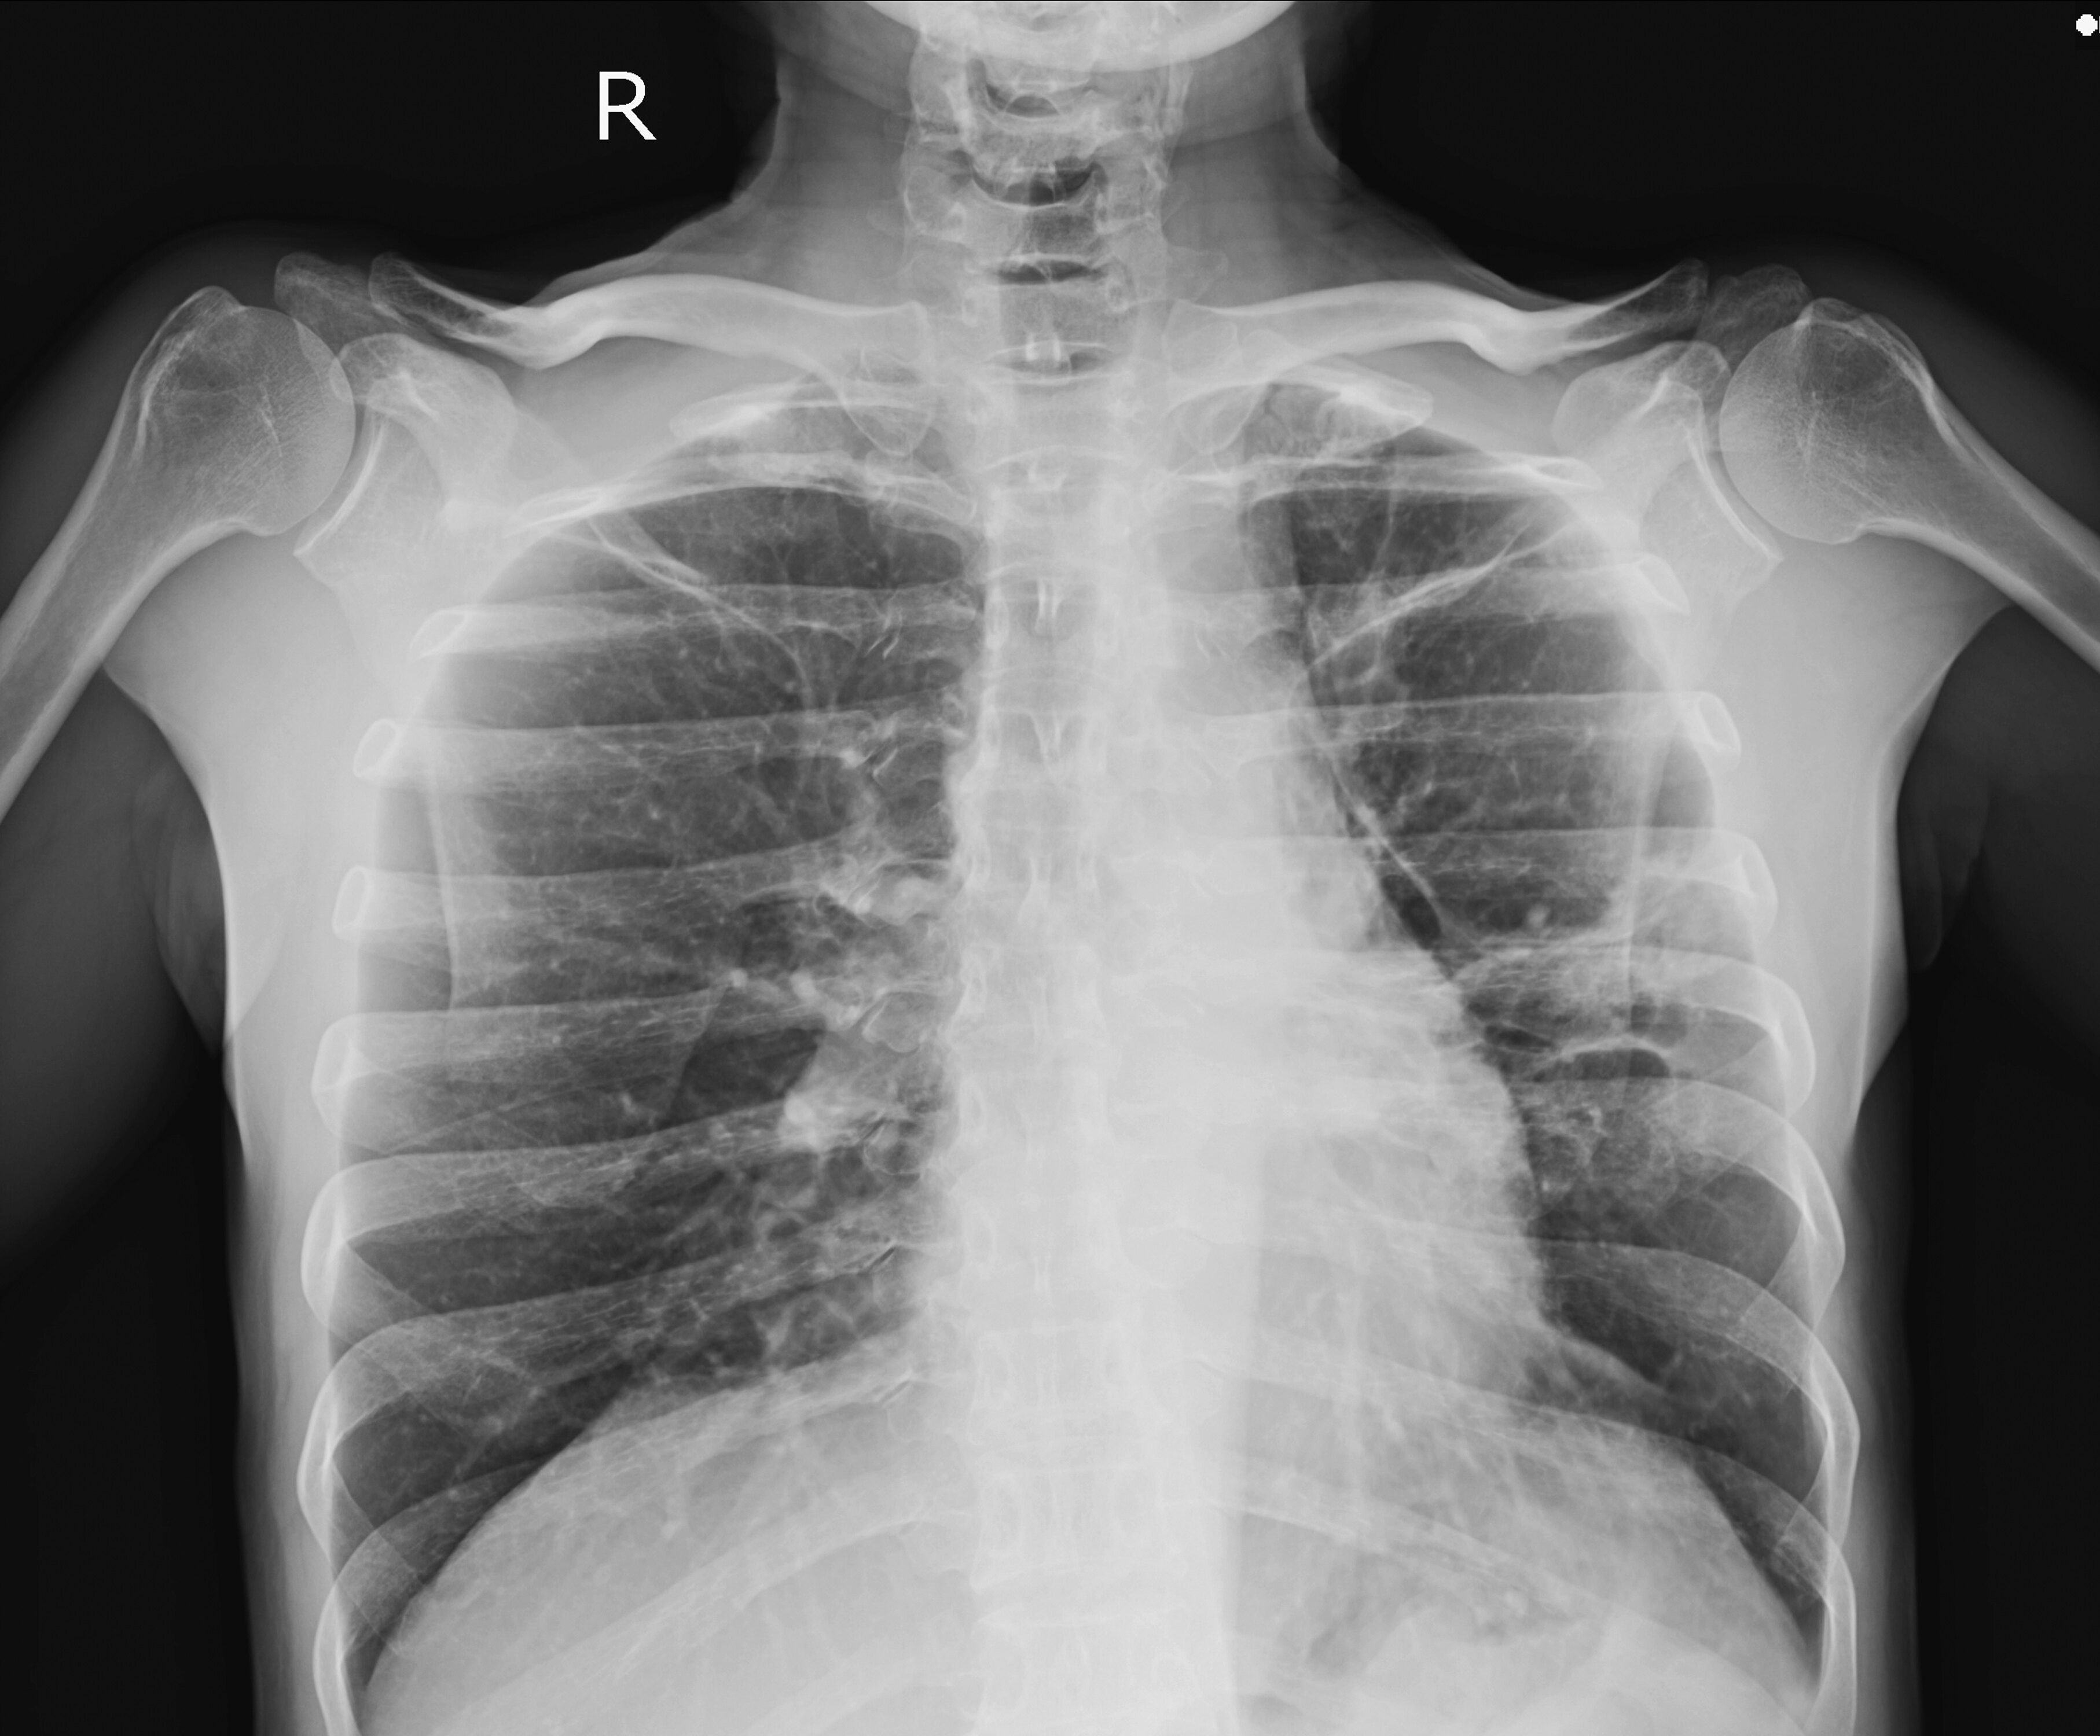

王女士今年体检查出肺结节,报告显示为多发性实性结节,大小约3-4毫米,她接连去了好几家医院反复咨询,均被医生告知“定期复查就行”,但她仍然放心不下。近年来,像王女士一样被查出肺结节的人,大多都是谈结节色变,唯恐小小结节会发展为肺癌。今天我们就来说说什么是肺结节?它是否会癌变?对于肺结节的认知又存在哪些误区?

按照结节的大小来划分,直径小于3厘米的通常描述为结节灶;直径小于1厘米的描述为小结节;直径小于0.5厘米的描述为微小或细小结节。如果按照结节在影像学上的表现来划分,肺结节可分为实性结节和亚实性结节。实性结节即结节密度较高,不透明,似内部有填充物;亚实性结节的密度低于实性结节,且可进一步细分为纯磨玻璃结节和混合磨玻璃结节。

很多人可能都听说过“磨玻璃结节”的概念,但并不知道这具体代表什么。简单来说,密度高的影像在CT中为“白色”,密度低的影响在CT中则呈现“黑色”,而“磨玻璃结节”在CT中不是“非黑即白”的,而是表现为密度稍高、类圆形的云雾状影,与生活中所见到的磨砂玻璃相似,因此得名。其中,纯磨玻璃结节全部由磨玻璃成分组成,混合磨玻璃结节则由实性成分和磨玻璃成分混合而成。

一般情况下,8毫米以下的结节,发生恶变的风险较低,大多遵医嘱定期复查胸部高分辨薄层CT即可。注意,这里要做的CT是高分辨薄层CT而不是低剂量CT,因为低剂量CT由于降低了辐射剂量会影响清晰度;对于8毫米-3厘米的结节,由于发生恶变的风险会随着结节的增大逐渐升高,因此需根据结节的具体形态特点、随诊时结节形态的变化,以及患者的自身情况给出个体化建议;对于3厘米以上的不规则病灶,医生一般称之为肿物而非结节,通常建议手术治疗。

具体来说,对于实性、有钙化点、边缘规则的结节,包括陈旧病变、纤维结节等,不需要手术,可以定期观察。对于大于2厘米的磨玻璃结节,或大于1.5厘米的混合密度磨玻璃结节且其实性成分大于0.5厘米的,或实性成分大于2厘米的结节,或有毛刺、分叶的结节,均建议手术治疗或活检穿刺。